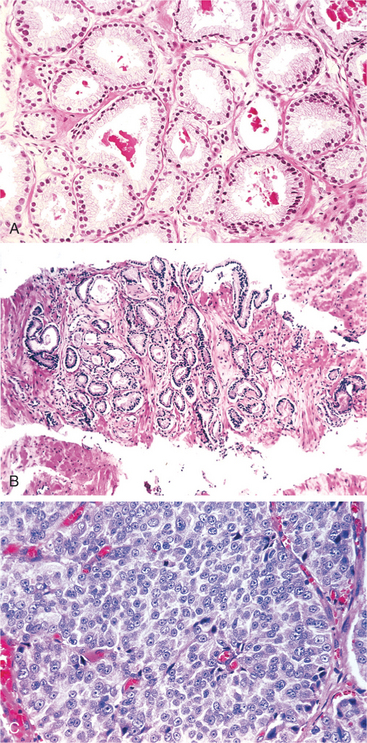

Prostate cancer can also metastasize to the lungs and liver. The Gleason score is used to grade prostate cancer cells on how they appear under a microscope (Fig. 19-5) and predict the likelihood of metastases (Box 19-2).

Figure 19-5 A, Low-grade (Gleason score 2) prostate cancer consisting of backto-back, uniformly sized, well-differentiated (resembling normal cells) malignant glands. B, Variably sized, more widely dispersed glands of moderately differentiated adenocarcinoma (Gleason score 6). The higher the Gleason score, the more abnormal and poorly differentiated the cells, the more aggressive the tumor is likely to be. C, Poorly differentiated adenocarcinoma composed of sheets of malignant cells (Gleason score 10). (From Kumar V: Robbins and Cotran: pathologic basis of disease, ed 7, Philadelphia, 2005, WB Saunders.)